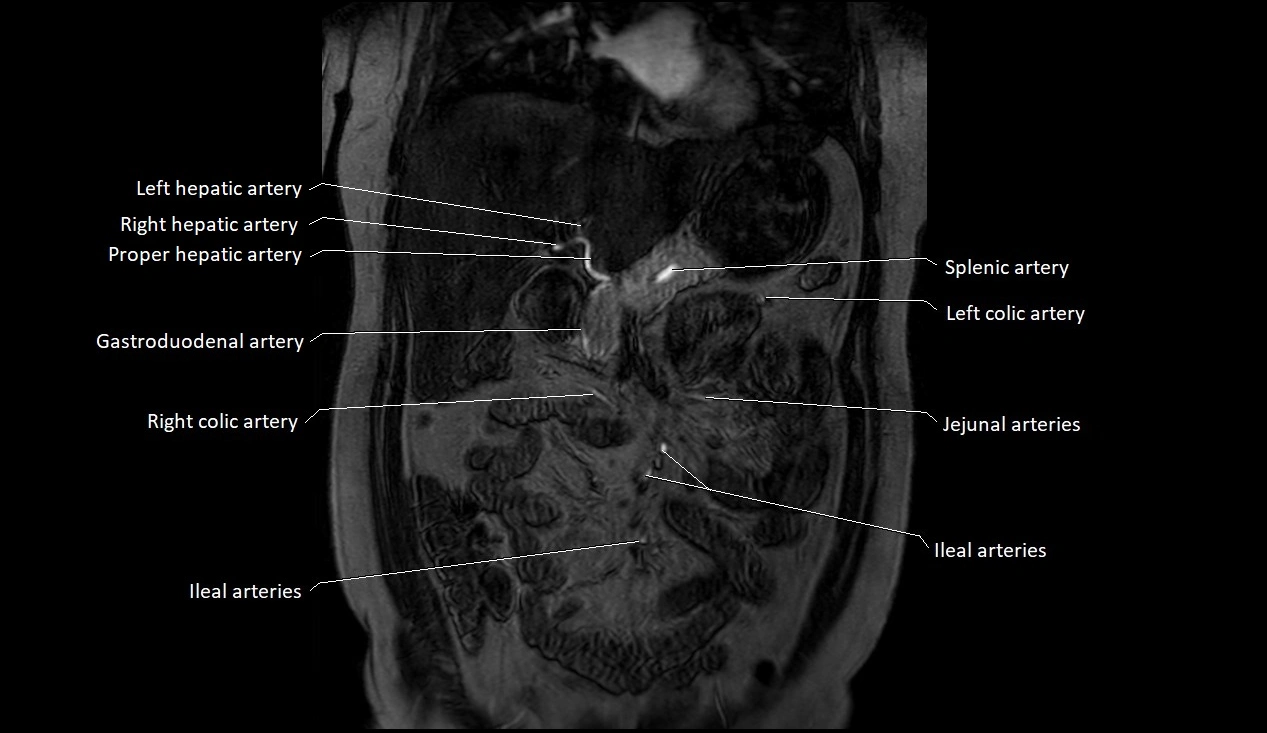

MRA (Magnetic Resonance Angiography):

• Contrast-enhanced MRA provides high-resolution imaging of the aorta and its branches

• Allows 3D reconstruction of visceral, parietal, and terminal branches

• Excellent for evaluating aneurysm size, dissection flap, stenosis, or preoperative planning

• Non-invasive alternative to conventional angiography

MRI images

image